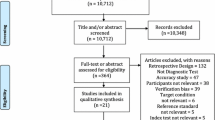

Patient recruitment, examination, and data acquisition for this prospective study were performed between May 2018 and May 2019. Eleven healthy volunteers (Group I; male and female) aged between 18 and 45 years were enrolled for reliability testing. Subjects in Group I had no history of knee injury or surgery and a standard clinical examination of the knee revealed no pathologic findings. Additionally, ten consecutive patients presenting for a follow-up (FU) examination (minimum 12 months FU) after anterior cruciate ligament reconstruction and all-inside lateral meniscal radial tear repair were asked for participation for validity testing (Group II). Lateral ME measurement is of high interest in patients undergoing radial meniscal tear repair since a correlation between lateral ME and radial meniscal tear healing is assumed [15]. Both knees were examined in all subjects, so that data of 22 and 20 knees were available in Group I and Group II, respectively (Fig. 1). In both groups, neutral leg alignment, clinically assessed using the methods described by Navali et al. [20] and Hinman et al. [21], was required for participation. Clinical signs of knee joint osteoarthritis [22, 23] as well as obesity (BMI ≥ 30) were criteria for exclusion. Lateral ME, measured under two loading conditions using US (Group I and Group II) and MRI (Group II only), served as the main outcome parameter.

Group assignment. a Reliability testing based on Group I. Ultrasound (US) images were acquired twice in an unloaded condition and once in a loaded condition by each observer. Intrarater reliability testing was based on repeated measurements in the unloaded condition. Interrater reliability testing was based on measurements taken by each observer in the unloaded and loaded condition. “n” represents the number of images acquired by each observer in the respective loading condition. b Validity testing based on Group II. US and MRI images were acquired in both knees of all subjects in the unloaded and loaded condition. “n” represents the number of images acquired for each imaging modality in the respective loading condition